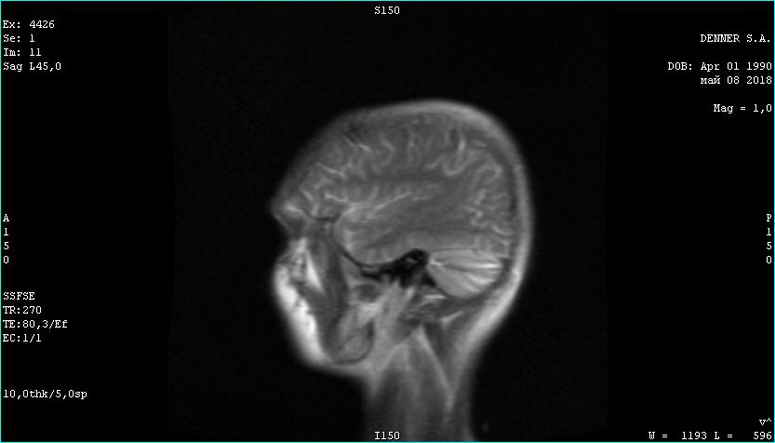

Фома неверующий. Вот этого парня я сейчас лечу. Опухоль за 3 месяца лечения уже не активна. Частично пошло ее разложение. Тремор сердца исчез. Походка восстановилась. В августе скину новое мрт с результатом лечения. Динамика на снимке. Ядро опухоли гибнет за 3 месяца. Господа!!!! За 3 месяца!

Вверху февраль 2018. Внизу май 2018

Опухоль контраст не накапливает. Связи с костью уже не имеет. Головка опухоли начала разлагаться. Врачи в шоке. А я злорадствую. Сергей мне поверил и сейчас копает огород на Алтае, хотя должен был умереть в июле. Моя карма получила жирный плюс...

Фото мрт сделаны немного в разных ракурсах, (зачем, непонятно-наверное чтобы не признавать эффект оздоровления ), но положительная динамика все равно видна. И пациент начал жить полноценной жизнью - секс, загар, копание огородов и рыбалка...